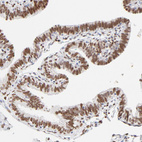

Immunohistochemistry analysis in human fallopian tube and liver tissues using HPA003505 antibody. Corresponding PBX1 RNA-seq data are presented for the same tissues.